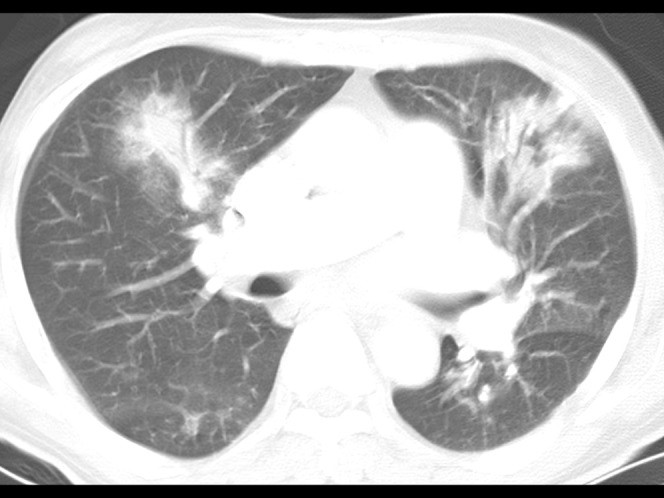

COVID19-CT dataset [51]: The dataset consists of a total of 746 CT images. There are 349 CT images of patients with COVID-19 and 397 CT images showing Non-COVID-19, but other pulmonary diseases. The positive CT images were collected from preprints about COVID-19 on medRxiv and bioRxiv, and they feature various manifestations of COVID-19. Since the CT images were taken from different sources, they have varying sizes between and . Figure 8 shows example CT images from the COVID19-CT dataset.

On the COVID19-CT dataset, the overall performance with respect to all evaluation metrics is inferior to that on the SARS-CoV-2 dataset. This can be attributed to the cross-source heterogeneity of the CT images in the dataset. The Non-COVID-19 CT images were taken from different sources and show diverse findings which pose difficulty to distinguish between COVID-19 and other findings associated with lung diseases due to the potential overlap of visual manifestations (see Figure 8). Another reason is that, the CT images in the COVID19-CT dataset show strong variations in contrast, variable spatial resolution and other visual characteristics, which could affect the model’s ability to extract more discriminative and generalizable features.